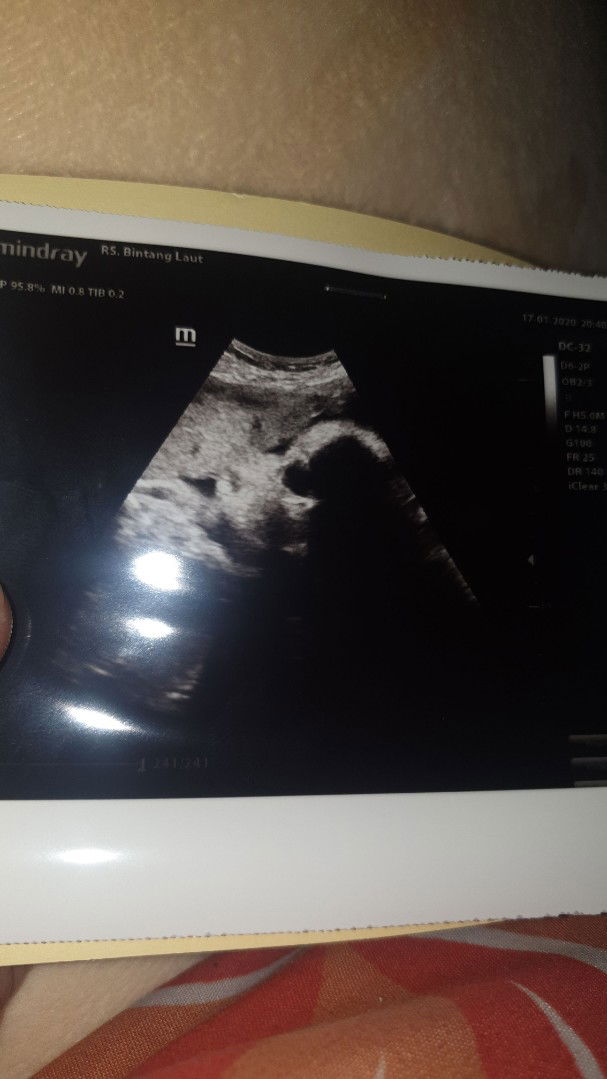

??

Gagal 4D krna ketutup plasenta mukanya dede?? btw itu wkt usia 30 week, semangat bundsay yg hpl nya maret??